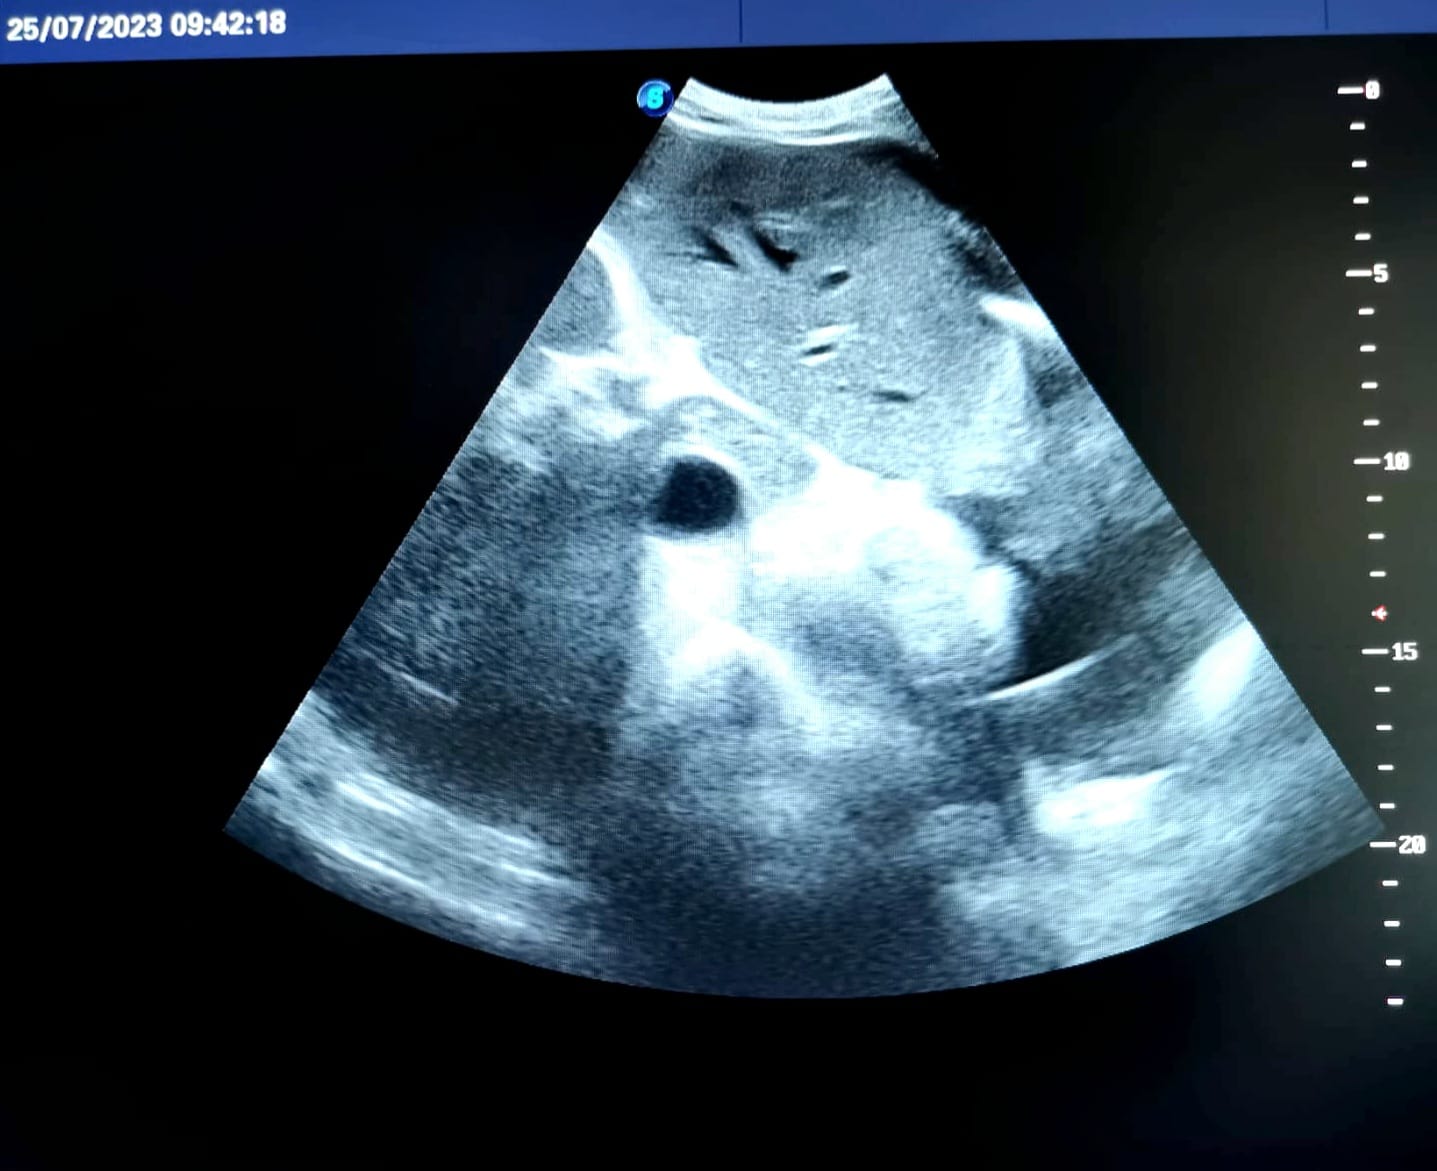

- 25 июля к нам обратился 55-летний мужчина. Он много лет игнорировал симптомы, которые явно говорят о том, что с печенью не всё в порядке: боль в правой половине живота, снижение аппетита, утомляемость, нарушение сна, желтушность кожи. Эти симптомы проявляются потому, что ресурсы оставшихся клеток печени иссякают и свои функции орган выполняет с трудом, - рассказала Рузана Минахметовна. – На УЗИ по увеличению размеров печени, по её неоднородной структуре и неровному бугристому контуру мы чётко видим, что это цирроз.

И подчеркнула, что при циррозе печени также могут отмечаться признаки портальной гипертензии: асцит, увеличение селезенки. В этом тяжёлом случае (на снимке 3-я терминальная стадия заболевания), вернуть печень в нормальное состояние уже невозможно. Пациенту предстоит серьёзное лечение в стационаре.